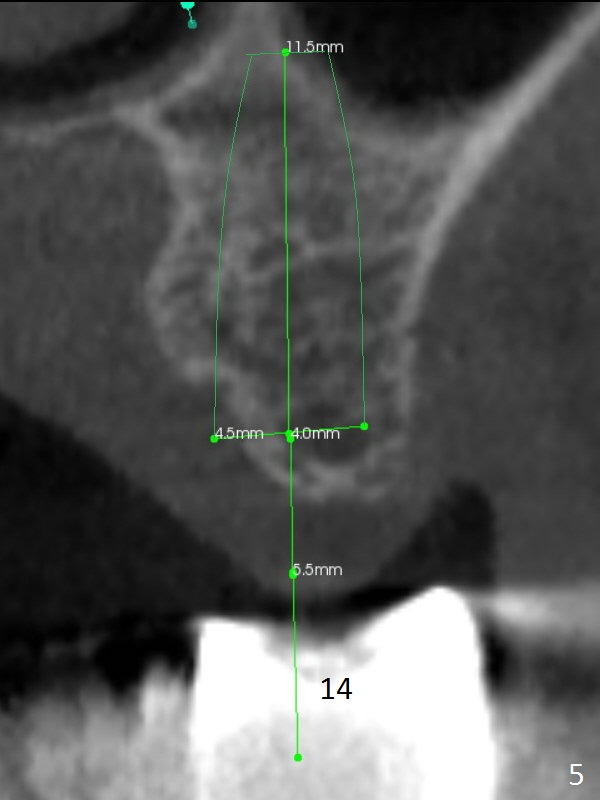

While the 64-year-old woman is undecided on the lower right quadrant treatment, she has had periodic pain and swelling in the upper left quadrant (Fig.1). CBCT sagittal sections show periapical radiolucency at #13 and bone loss distal to #15 palatal root (Fig.2,7). Endodontic treatment is the 1st option to save the long bridge (#9-15, Fig.1).

More thorough option is to section between #11 and 12, remove #13 and 15 retainers and determine salvageability of #13 and 15 abutments. Place implants between #12 and 15 if necessary (Fig.3-6 coronal sections; B: buccal).